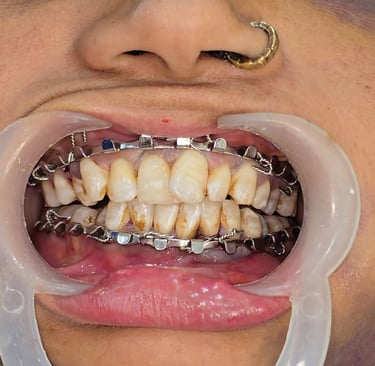

Initial Stabilization with Intermaxillary Fixation (IMF)

IMF was done to achieve temporary occlusion and stability.

Elastic bands were used to immobilize the segments.